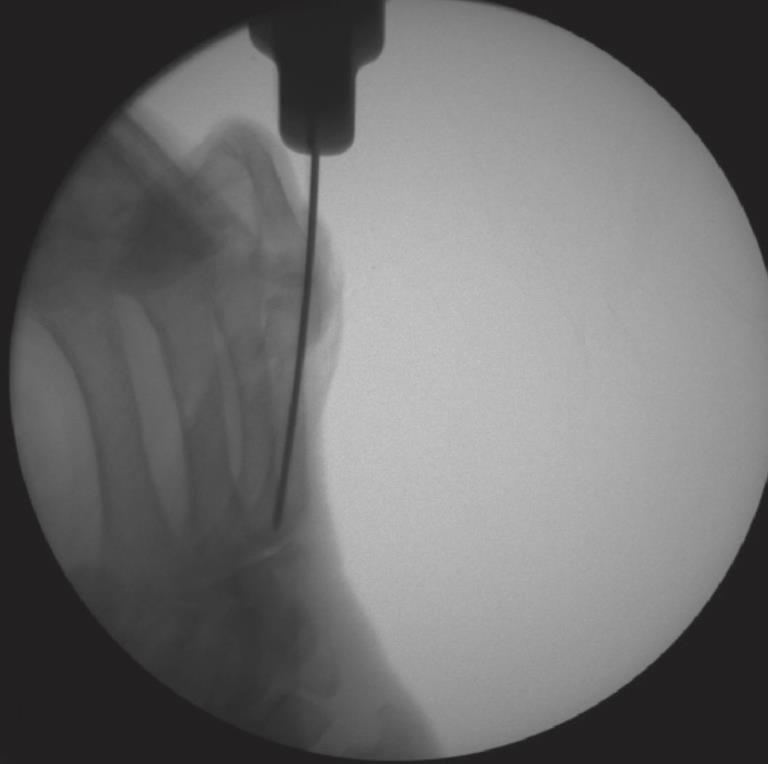

• Phalanx

• fully flex the metacarpophalangeal joint mark the dorsal third of the metacarpal head

• expose the base of the proximal phalanx by subluxing to allow percutaneous access to the proximal articular surface

• the illustrated surgical technique uses an antegrade approach, described as less traumatic to the PIP joint

• Phalanx Technique

• step 1

• insert a 1.6mm k-wire into the subluxed proximal phalanx base in line with the medullary canal of the proximal fragment

• advance the k-wire to the fracture site under fluoroscopy, reduce the fracture, and advance the k-wire into the proximal phalanx head